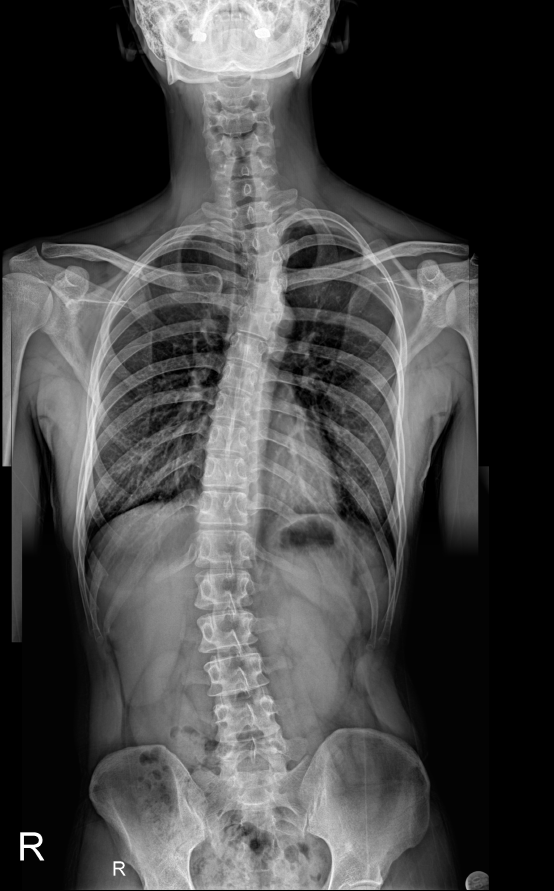

나는 현재 척추측만증을 앓고 있다.

현재 척추가 사진과 같은 상태인데 척추를 교정하기 위해 필라테스 센터에서 체형교정 1:1 수업을 신청했다.